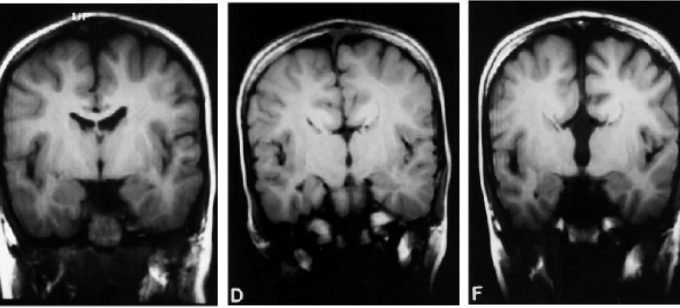

Paradoxical expectation: oscillatory brain activity and social interaction in schizophrenia